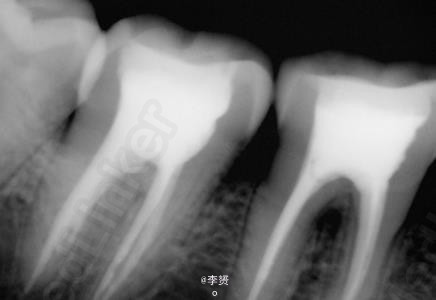

患者,女,30岁,右下第一磨牙疼痛来诊。平素体质一般,无药物、食物过敏史,无高血压、心脏病等系统病史。近期出现冷热刺激痛,根尖脓肿。

诊断 处理

在显微镜下进行断针取出